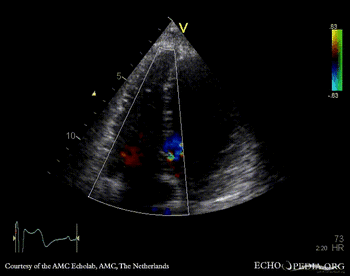

Double chambered right ventricle

A4CH with Color Doppler: high velocity signal in right ventricle Continuous-wave Doppler signal of gradient in right ventricle